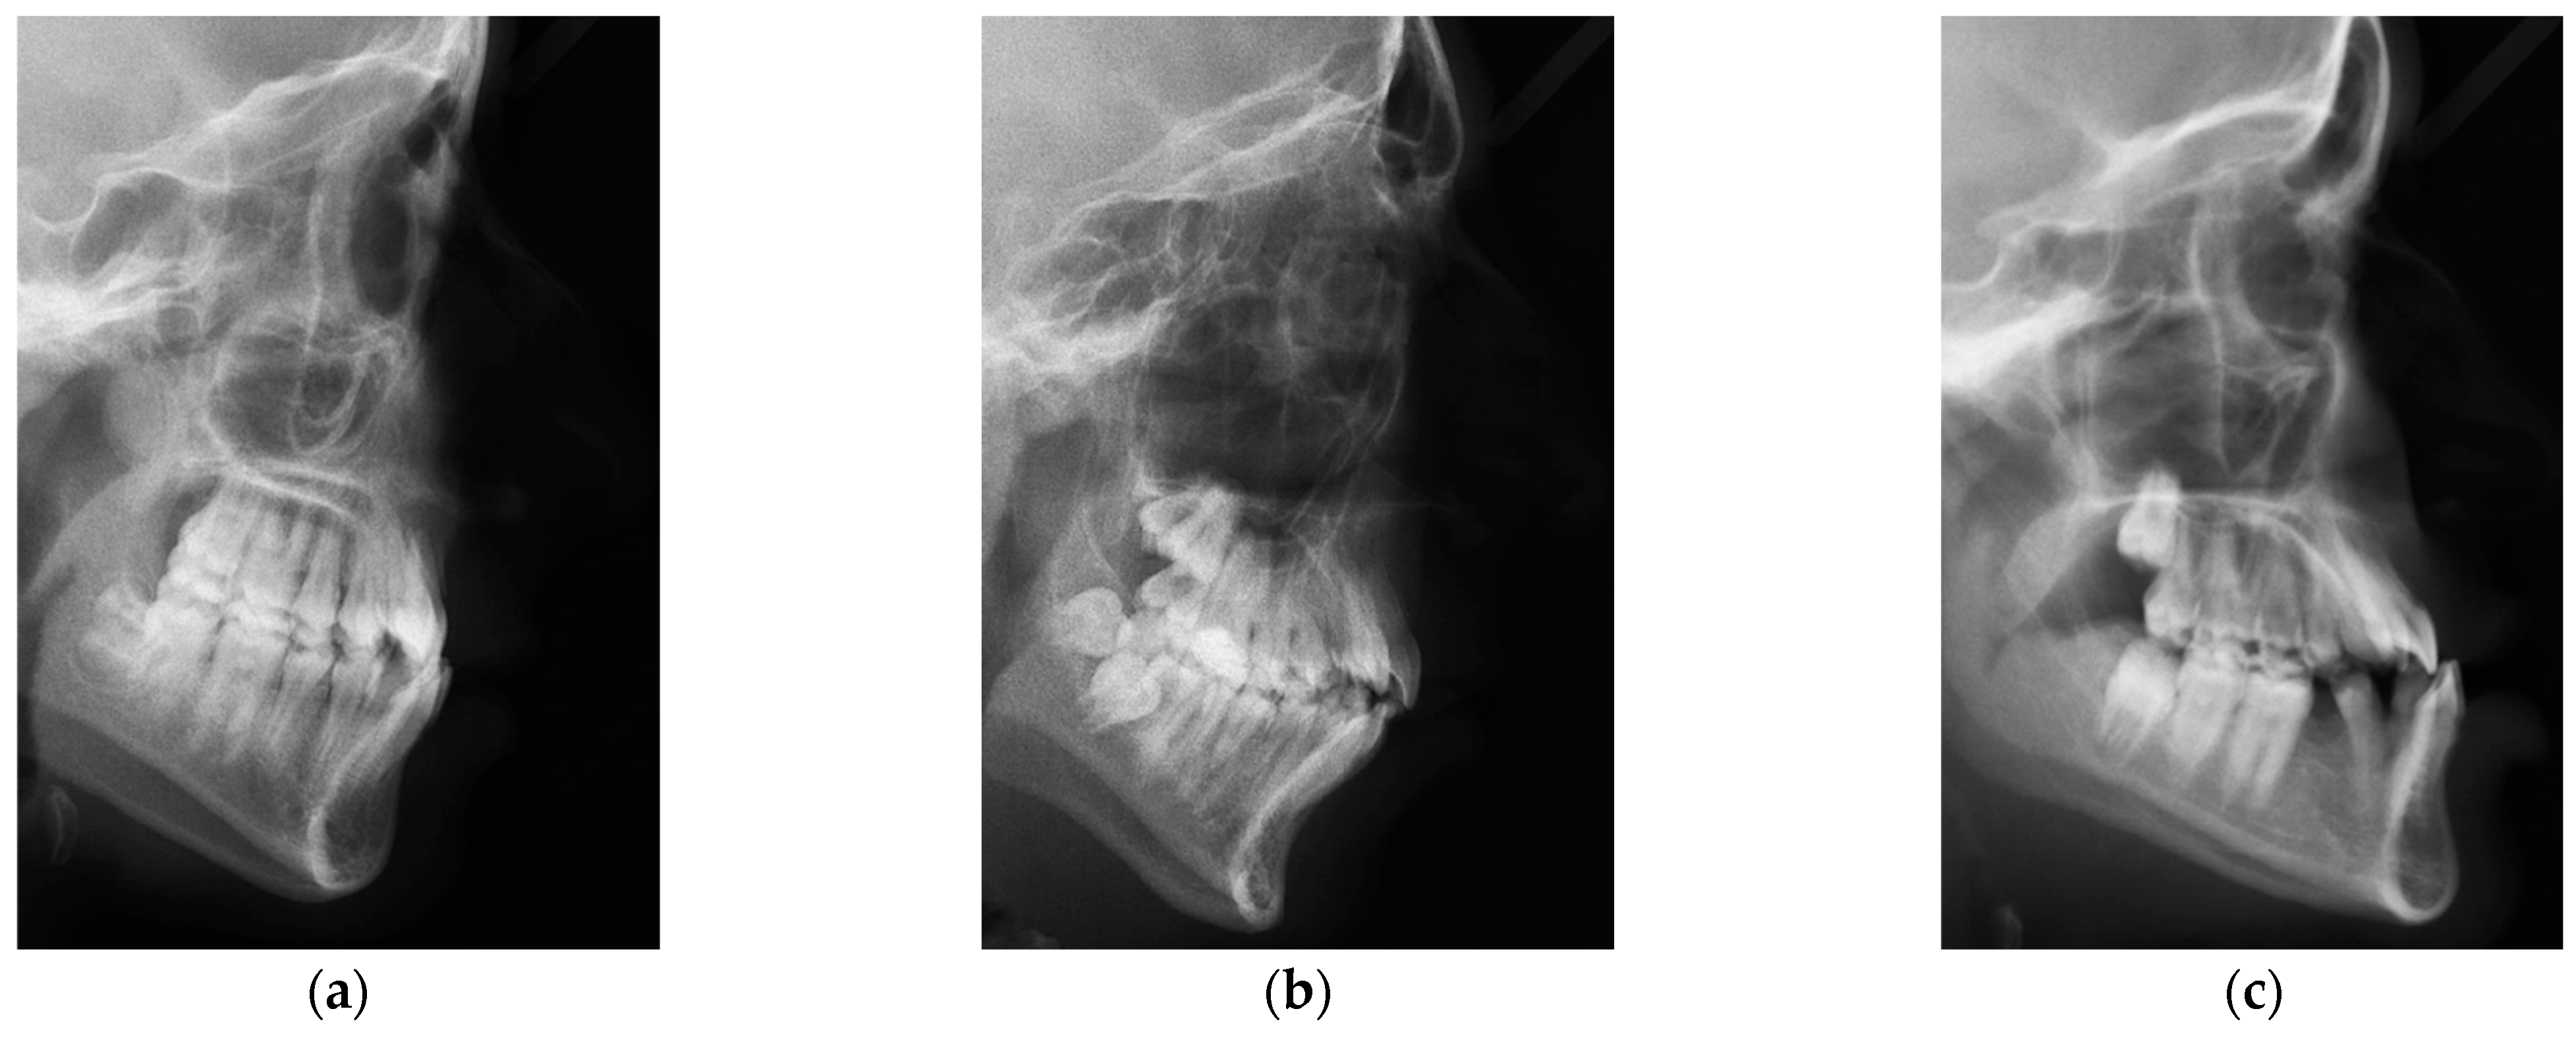

2.1. ISBI Dataset

2.2. Dicle Dataset